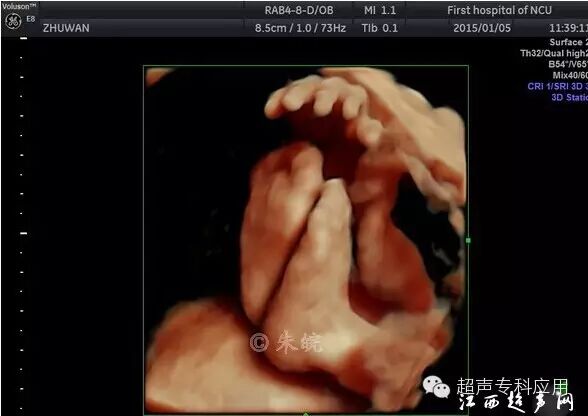

1.1 表面结构的成像 这是三维超声最初在胎儿显像的应用。早孕期可显示整个胎儿的形态以及头颅、腹壁、四肢等;中孕期则能显示胎儿头面部、手指(脚趾)等相对细小的结构。这些表面结构的三维图像,客观逼真,一旦存在胎儿体表的畸形,如唇裂、脑膨出、脊柱裂、脐膨出、腹裂、肢体或手脚畸形,三维成像能够让孕妇及家属一目了然,让产科医生或儿科医生更结合实际情况进行咨询,方便选择下一步的处理方案。虽然三维超声对体表畸形的诊断可能并不比二维超声提供更多信息,这些体表畸形可能在二维声像图上也较容易显示,但孕妇及家属却不理解二维图像,难以想象畸形外观如何、有多严重。为了更人性化的服务,目前,也有不少医院或产院对孕妇提供“胎儿照相”;四维超声观看胎儿运动并录像,以留作纪念。三维表面成像的重要条件是感兴趣区域前方一定要有足够的羊水,而且不能被肢体、脐带等遮挡。羊水过少或晚孕期胎儿充满官腔时,三维表面成像则有较大困难。